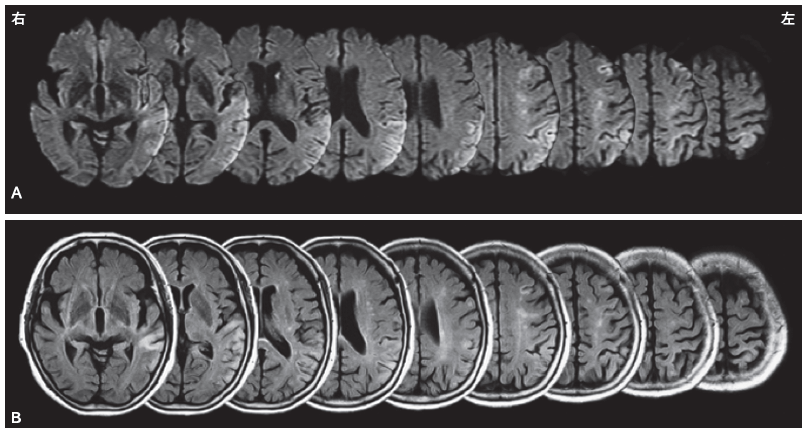

現病歴:夜間に右手の脱力を自覚し,当院に救急搬送された.第7病日に一過性の右完全片麻痺と全失語が出現し,第14病日の頭部MRI(図1)で左の前頭葉と頭頂側頭葉に梗塞巣を認めた.第8病日までに麻痺はごく軽度となったが,後述するような動作の拙劣さを右手に,道具把握の障害を両手に認めたため,リハビリテーションを開始した.

A:拡散強調画像,B:FLAIR 画像.